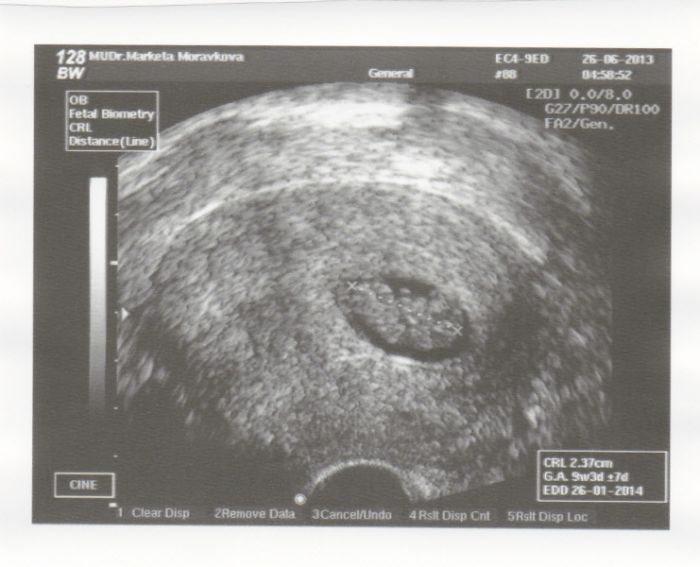

ze včerejšího UZ :-) mimísek se pěkně předváděl :-D kopal nožkama a rozhazoval ručkama :-)

Krásná fotečka Ajulko